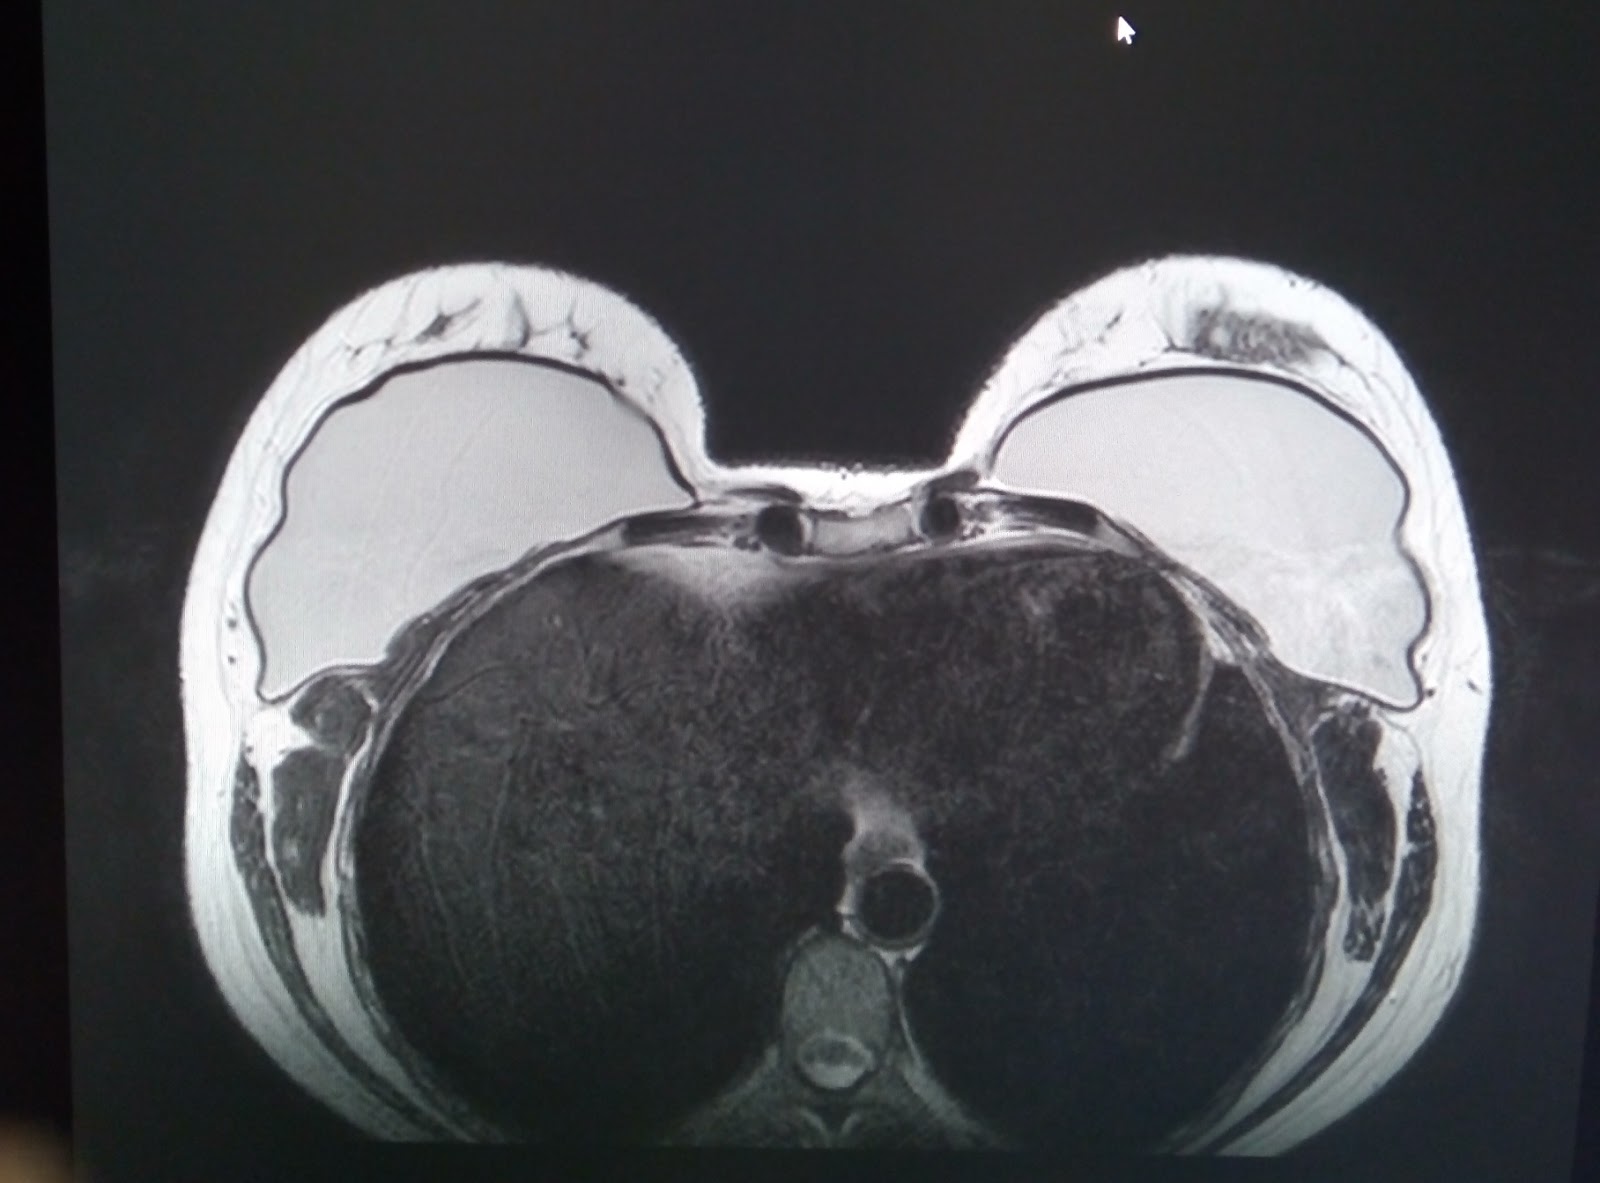

Магнитно-резонансная томография молочной железы: что нужно знать